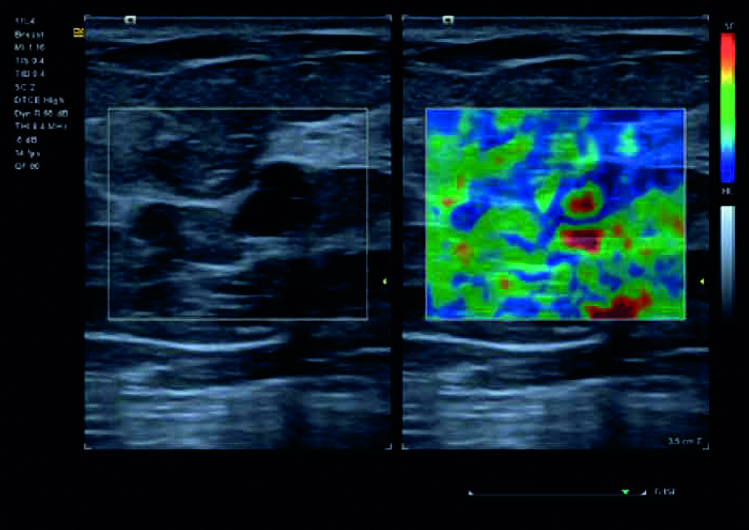

Una valutazione qualitativa del tessuto ad altissima risoluzione con eSieTouch elasticity imaging per la valutazione e la caratterizzazione delle lesioni del seno.